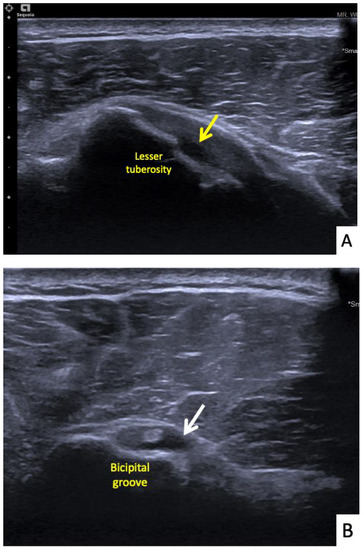

The fifth case was a 68-year-old Thai female who began to feel right shoulder pain with limited range of motion 24 h after a second dose of AstraZeneca vaccine. She had had no shoulder pain before the vaccination. The vaccination landmark was 3 fingerbreadths below the acromial process and the needle direction was 45 degrees cephalad to the skin. Her symptoms had persisted for 14 days without improving. They were worse at night, and she could not lay on her right shoulder. She decided to see an orthopedist and the clinical examination showed tenderness at the deltoid muscle. She had a full range of shoulder motion, but with pain at some points. She was sent for ultrasonography which showed a thin layer of subdeltoid bursal fluid and a partial thickness tear of the subscapularis tendon (Figure 6A,B). She was treated with oral prednisolone (30 mg/day) for 5 days and her symptoms improved a week later.

Figure 6.

Ultrasonographic images of the right shoulder of Patient 5. (A) A longitudinal ultrasonographic image over the lateral aspect of the left proximal humerus with the patient in supination showing a small amount of fluid (yellow arrows) in the mildly distended subdeltoid bursa. (B) A transverse ultrasonographic image over the lesser tuberosity of the right shoulder with the patient in the external rotation position showing a partial thickness, articular surface tear at the footprint of the subscapularis tendon (white arrows).